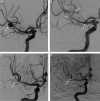

Some studies have reported the efficacy and safety of the Atlas stent and the Leo Baby stent-assisted coiling (SAC) of intracranial aneurysms arising from small cerebral vessels. The authors aimed to compare the clinical performance of the Atlas and the Leo Baby stents in small parent arteries.

Methods and materials: Between January 2019 and November 2022, 56 patients at our centre were treated using either Atlas or Leo Baby SAC of intracranial aneurysms arising from small parent vessels (<2 mm). The clinical and angiographic imaging data of the two cohorts were retrospectively collected and comparatively analyzed.

Results: A total of 56 patients were included in this study. Thirty-two patients were treated with the Atlas SAC, and 24 patients were treated with the Leo Baby SAC. The mean age of the Atlas stent cohort was older, and the mean aneurysm size was smaller than the Leo Baby stent. The immediate complete occlusion rate was 68.6% in the Atlas stent cohort and 62.5% in the Leo Baby stent cohort. The mean angiographic follow-up time for Atlas stent cohort was 8.9±2.5 months, and the final aneurysm complete occlusion rate was 81.0%. The mean follow-up time for Leo Baby stent cohort was 18.9±6.0 months, and the final aneurysm complete occlusion rate was 83.3%.

Conclusions: At the final follow-up, the Atlas or the Leo baby stent SAC of intracranial aneurysms with small parent vessels resulted in favourable angiographic results and clinical outcomes, with a low rate of associated complications.